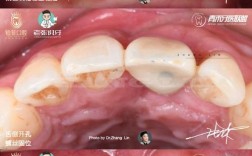

- 原理: 这里通常指的是全瓷固定桥,需要将缺牙位置相邻的1-2颗健康牙齿(作为基牙)磨小,然后制作一个包含假牙和覆盖在基牙上的全瓷冠的整体结构(桥体),粘接固定在磨小的基牙上。

- 注意:全瓷牙也可以指单颗全瓷冠(用于修复单个牙齿缺损或变色),但与种牙对比时,通常是指用于修复缺失牙的“全瓷桥”。

- 需要磨削健康邻牙: 这是最大的缺点!为了给桥体提供支撑,必须磨小(切削)旁边健康的牙齿,这会损害这些牙齿的结构,增加它们未来发生龋坏、牙髓炎、需要根管治疗甚至折裂的风险。